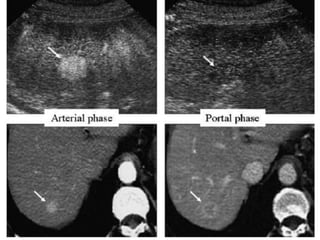

Vascularity of HCC

CONTRAST WASHOUT IN

HCC

Arterial Phase   Portal Venous Phase

CONTRAST WASHOUT IN HCC Arterial Phase Portal Venous Phase